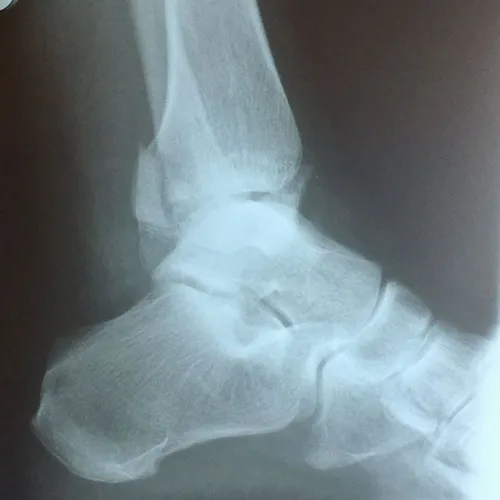

CT scan and Xray sagittal views of severly displaced posterior tibial malleolar fracture with comminution. This type of injury can cause significant problems in the future with disability if not treated with surgery to reduce the fracture and fixate.

Trimalleolar fractures involve fracture of the medial and lateral malleoli

along with a fracture of the posterior lip of the tibial

plafond; (posterior malleolar fracture). Fracture results from avulsion

by the posterior tibiofibular ligament at its site of attachment to the

tibia. The irregularity in the tibial articular surface of the tibia is

brought against the weightbearing surface of the talus and with

motion and weightbearing severe DJD develops.